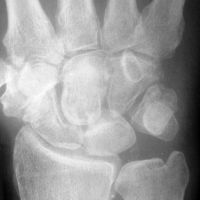

Plain films showed a well circumscribed lobular

lucency in the capitate and STT osteoarthritis. |

| MRI was

interpreted as inconclusive, differential including an

intraosseous cyst or giant cell tumor with cortical

thinning but no suggestion of malignancy. |